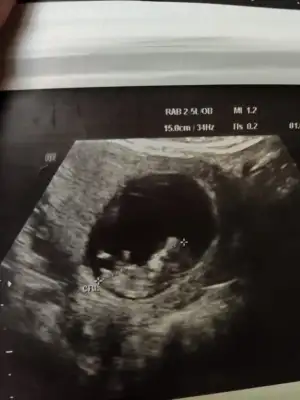

D Dantewn hello ben geldim. 11+3 ultrason fotoğraflarım burada. Doktor emin olamadı nub sanki çıkık ama tam açısında da değil zaten 12 den önce erken dedi ama diğer açıda da eğer o yatay olan nub ise birinci ultrasonla alakası yok. Sence nedir bu küçük ördek?